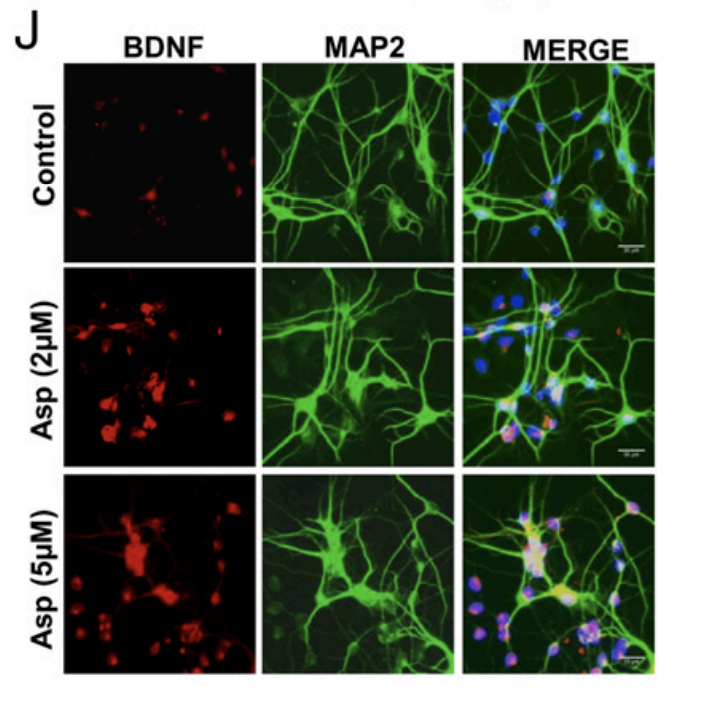

Aspirin has some strikingly potent effects on the brain.

⬨ It increases BDNF, responsible for growth of new brain cells

⬨ It increases neural plasticity in memory and higher thinking brain regions

In turn, it improves memory and cognition, again at lower doses.

⬨ It increases BDNF, responsible for growth of new brain cells

⬨ It increases neural plasticity in memory and higher thinking brain regions

In turn, it improves memory and cognition, again at lower doses.